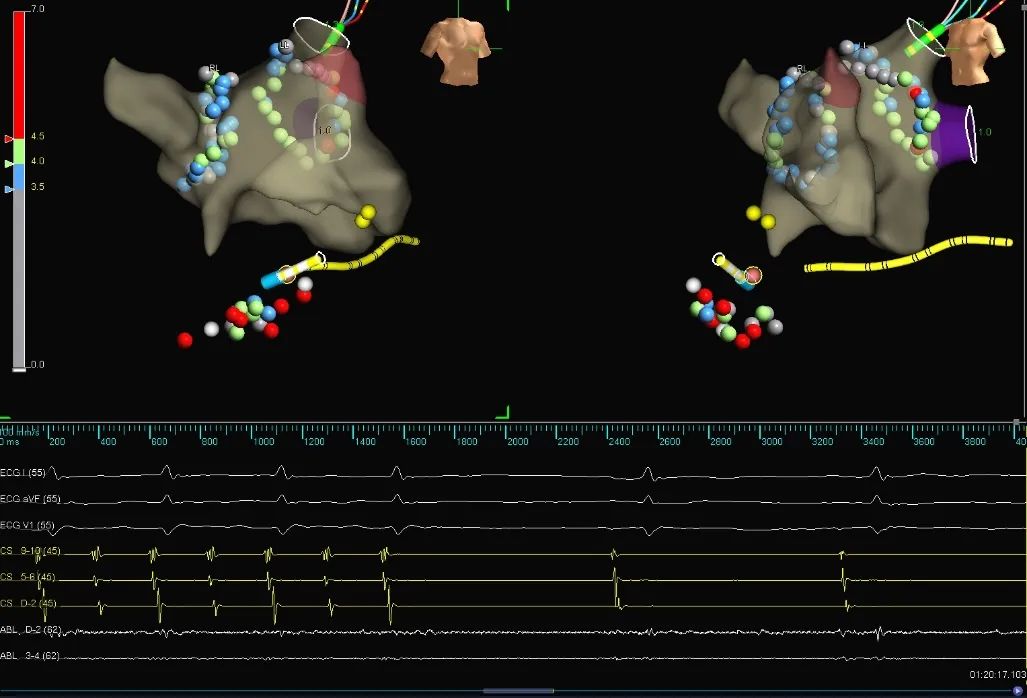

使用HD Gird重建左房三维模型,左房基质良好,首先完成肺静脉电隔离术(图1)。双侧肺静脉电隔离后,房颤转为房扑,经拖带标测提示为右房峡部依赖性房扑(图2),行三尖瓣峡部线性消融,消融过程中房扑终止转为窦性心律(图3),术后患者稳定窦性心律(图4)。

图1:双侧环肺静脉电隔离后转为房扑(房扑周长220ms)

图2:CS9,10及CS1,2拖带提示右房峡部依赖性房扑